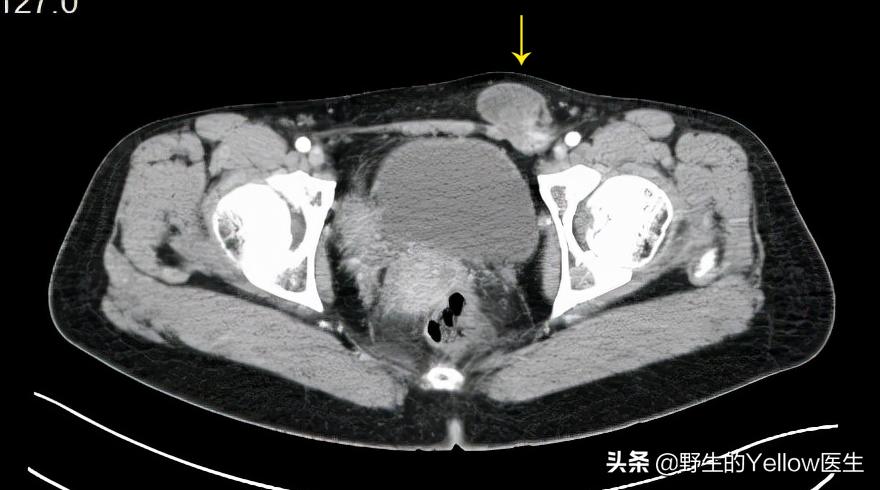

29岁,育龄期女性,7天前发现左侧腹股沟处包块突出,伴明显疼痛。

CT有什么发现?左侧腹股沟管可以见到软组织突出,考虑为卵巢,目前血供良好。

这个病人恰好子宫跟肾脏在分化的过程中发生了点小问题,导致了右侧单角子宫跟左侧异位肾。然后左侧的卵巢没有子宫帮忙固定,就在盆腔游离。结果她左侧腹股沟管比较薄弱,卵巢就掉进左侧腹股沟管,形成左侧腹股沟卵巢疝。

幸运的是,她及时就医。通过CT检查发现了问题所在,卵巢血供正常,没有缺血坏死。最终她接受了卵巢回纳跟腹股沟管修补手术。术后3天,快速康复出院了。